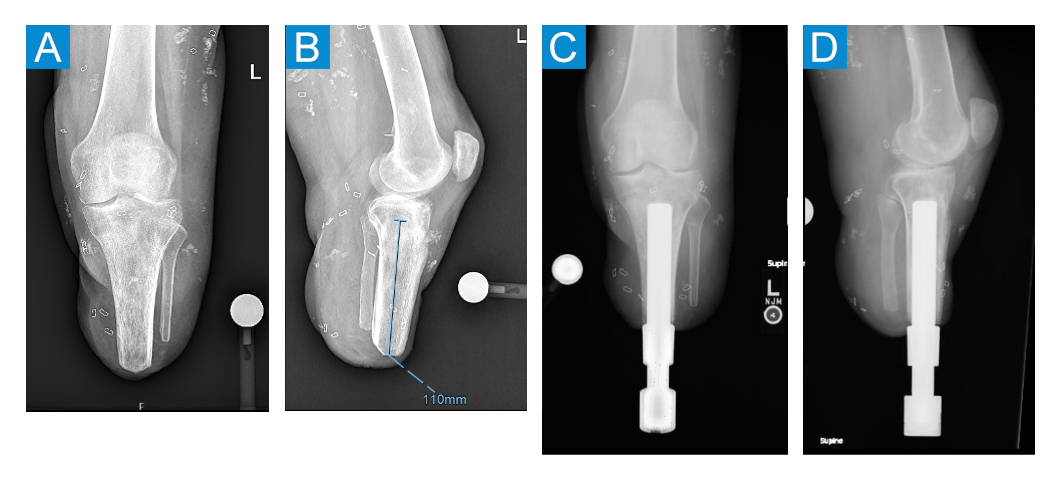

The custom-made tibial prostheses were designed to be inserted by impaction after reaming up to the appropriate diameter (Figure 3). This was a bilateral surgery with the right side and left side in succession. Considerable care was taken when handling her soft tissues due to poor skin quality. A percutaneous technique was used [1]. First, a 2.4-mm Steinmann pin was placed under fluoroscopy; next, a small 18-mm stoma was created. The tibial canal was sequentially reamed up to 19 mm in the distal 2 cm of her tibia. Then it was serially rasped and broached, increasing by 1 mm at a time, until 19 mm was achieved proximally at 100 mm, which was the planned length of the implant. The patient did not require peripheral nerve surgery such as target muscle reinnervation or regenerative peripheral nerve interface surgery.

Figure 3. A: Preoperative anteroposterior (AP) X-ray of left leg. B: Preoperative lateral X-ray of left leg. C: Postoperative AP X-ray of left leg. D: Postoperative lateral X-ray of left leg.